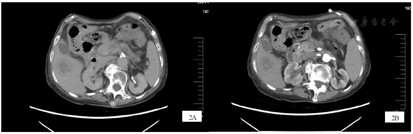

复查头MRI+MRA:双侧额顶叶、右侧侧脑室额角可见多发斑点及斑块状弥散受限,诊断脑内多发急性脑梗死灶;MRA示:双侧胚胎型大脑后动脉、基底动脉近端局限性狭窄;右侧椎动脉V4段移行为小脑后下动脉。(图1)。